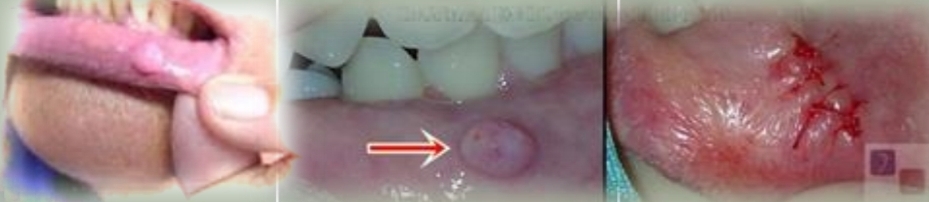

Pedunculated or sessile nodule, has a pink smooth surface, firm and non tender. Doesnt grow beyond a certain size

Irritation fibroma

Reactive hyperplastic lesion caused by chronic trauma and mimics tumor.

Limited growth potential

Treatment - Excisional biopsy, may reccur if irritation continues.

DD - Fibrosing mucocele, Peripheral ossifying fibroma, Giant cell fibroma, Benign submucosal neoplasm.